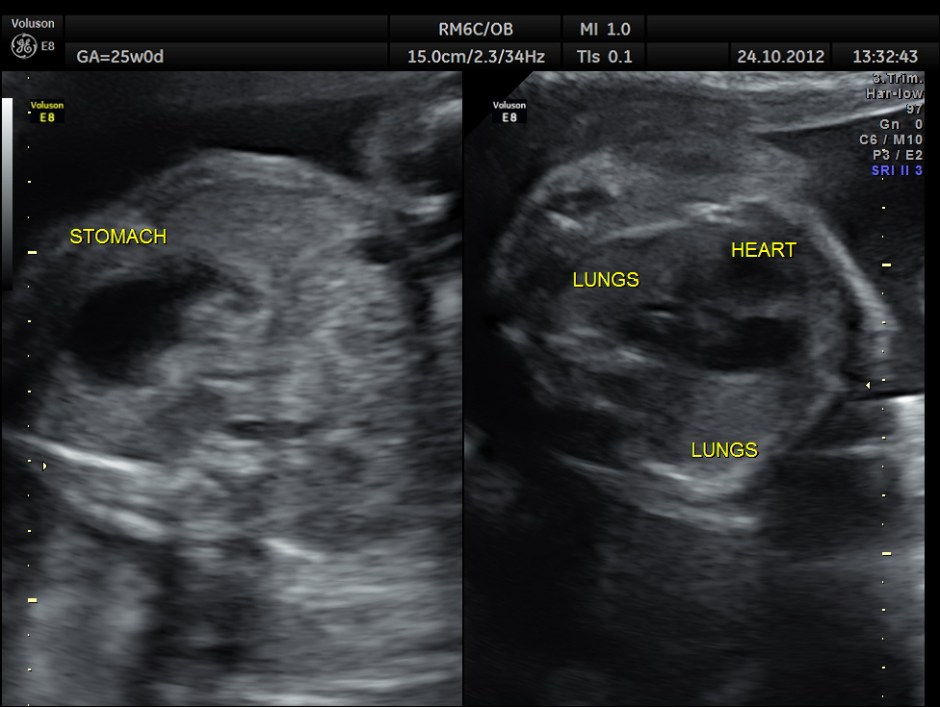

This was a 36 year old primi , non consanguinous ; she gave h/o taking sodium valproate for seizure disorder for the last 10 years.

The scan was done around 25 weeks of gestation :